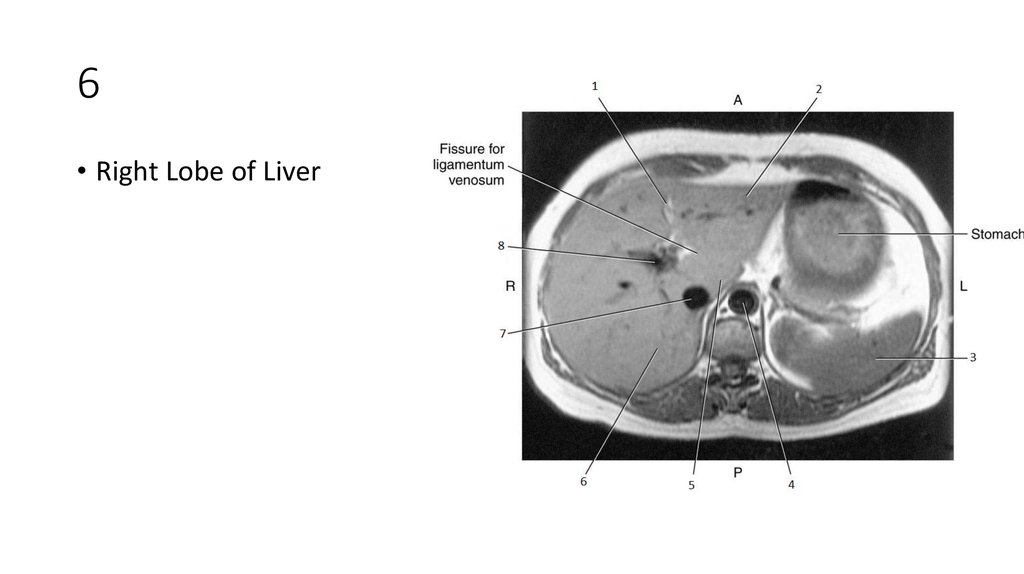

22. 4

23. 4

• Aorta

26. 6

27. 6

• Right Lobe of Liver